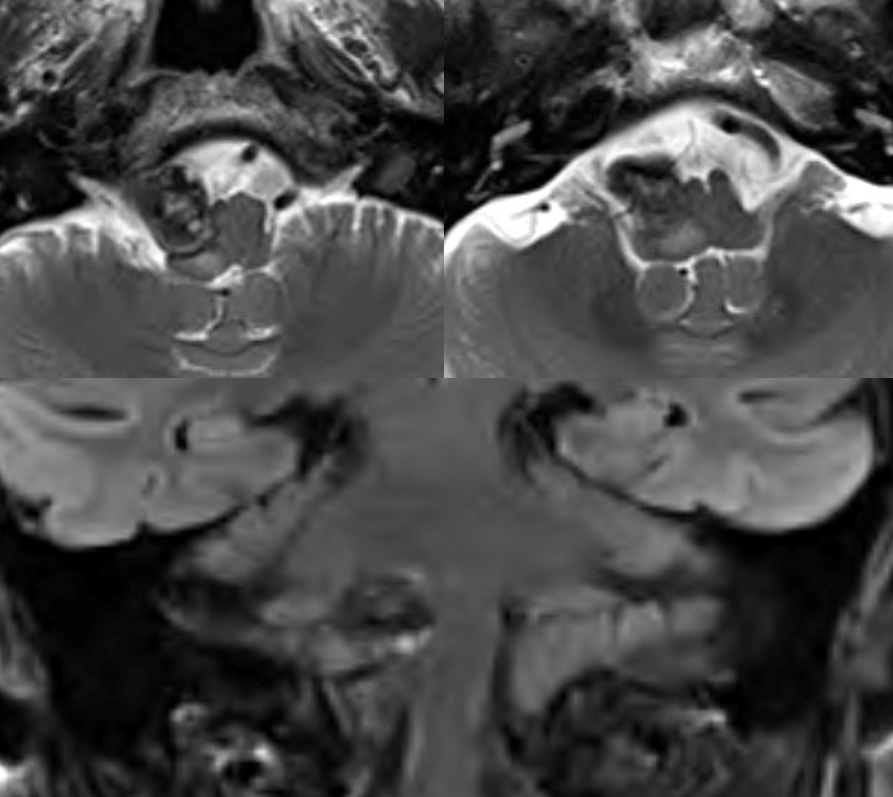

Mass effect/brainstem edema with a PICA aneurysm

Partially thrombosed even at smaller size is a sure sign of malignant / aggressive behavior

MRI is more important than angio here. A completely thrombosed aneurysm and improved brainstem are sure indications of success